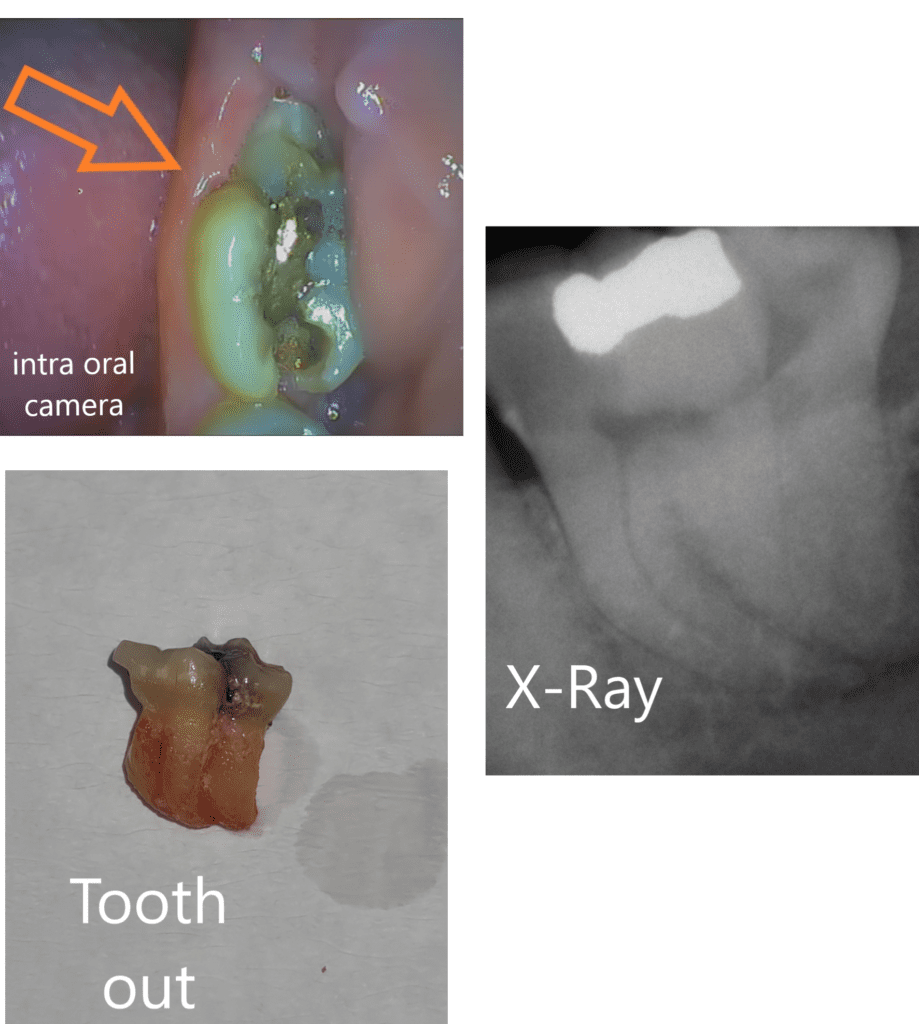

Fused Teeth Case Study

We treated a special case where a patient had a fused tooth (lower left 7 and lower left 8), a rare condition. The extraction was successfully completed, and the patient was relieved of their pain.